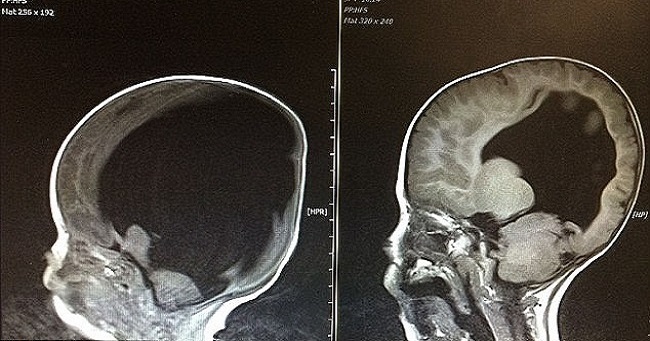

Noah Wall was not supposed to survive. Born to Shelly and Rob in 2012, Noah was born with just 2% of healthy brain tissue. Doctors had advised the parents that babies with such severe cases of hydrocephalus do not survive for long time after birth. Shelly and Rob had even gone through the extremely heart breaking job of choosing a baby coffin for Noah who was yet to be born.

Hydrocephalus is a condition in which fluid builds up in the brain and in Noah’s case; the fluid buildup in his brain had destroyed all but 2% of his brain cells. Effectively, Noah didn’t have any brain left and since it is perhaps the most important organ in the body, which controls all the other organs. It also helps in development of other organs and helps in physical and mental growth of an individual.

In Noah, that would be impossible and therefore doctors didn’t have much faith in his survival. But miracles happen and in Noah’s case, he was born on this Earth to survive and that’s what he did. But his survival for four years and continuing has baffled the doctors.

Now four years old, Doctors are stunned to see Noah, who has even learnt to count. His brain has started growing and is almost to its full function. The spina bifida condition has however left him on a wheelchair.

"No one can explain how this recovery happened as it’s so complicated. He still has fluid on the brain - his latest scan doesn’t look like yours or mine. But the prognosis is good. He could become a doctor or Prime Minister. Intellectually, we will have to wait and see what he is capable of" said Dr. Colin Shieff, consultant neurosurgeon and trustee of brain injury charity Headway UK.